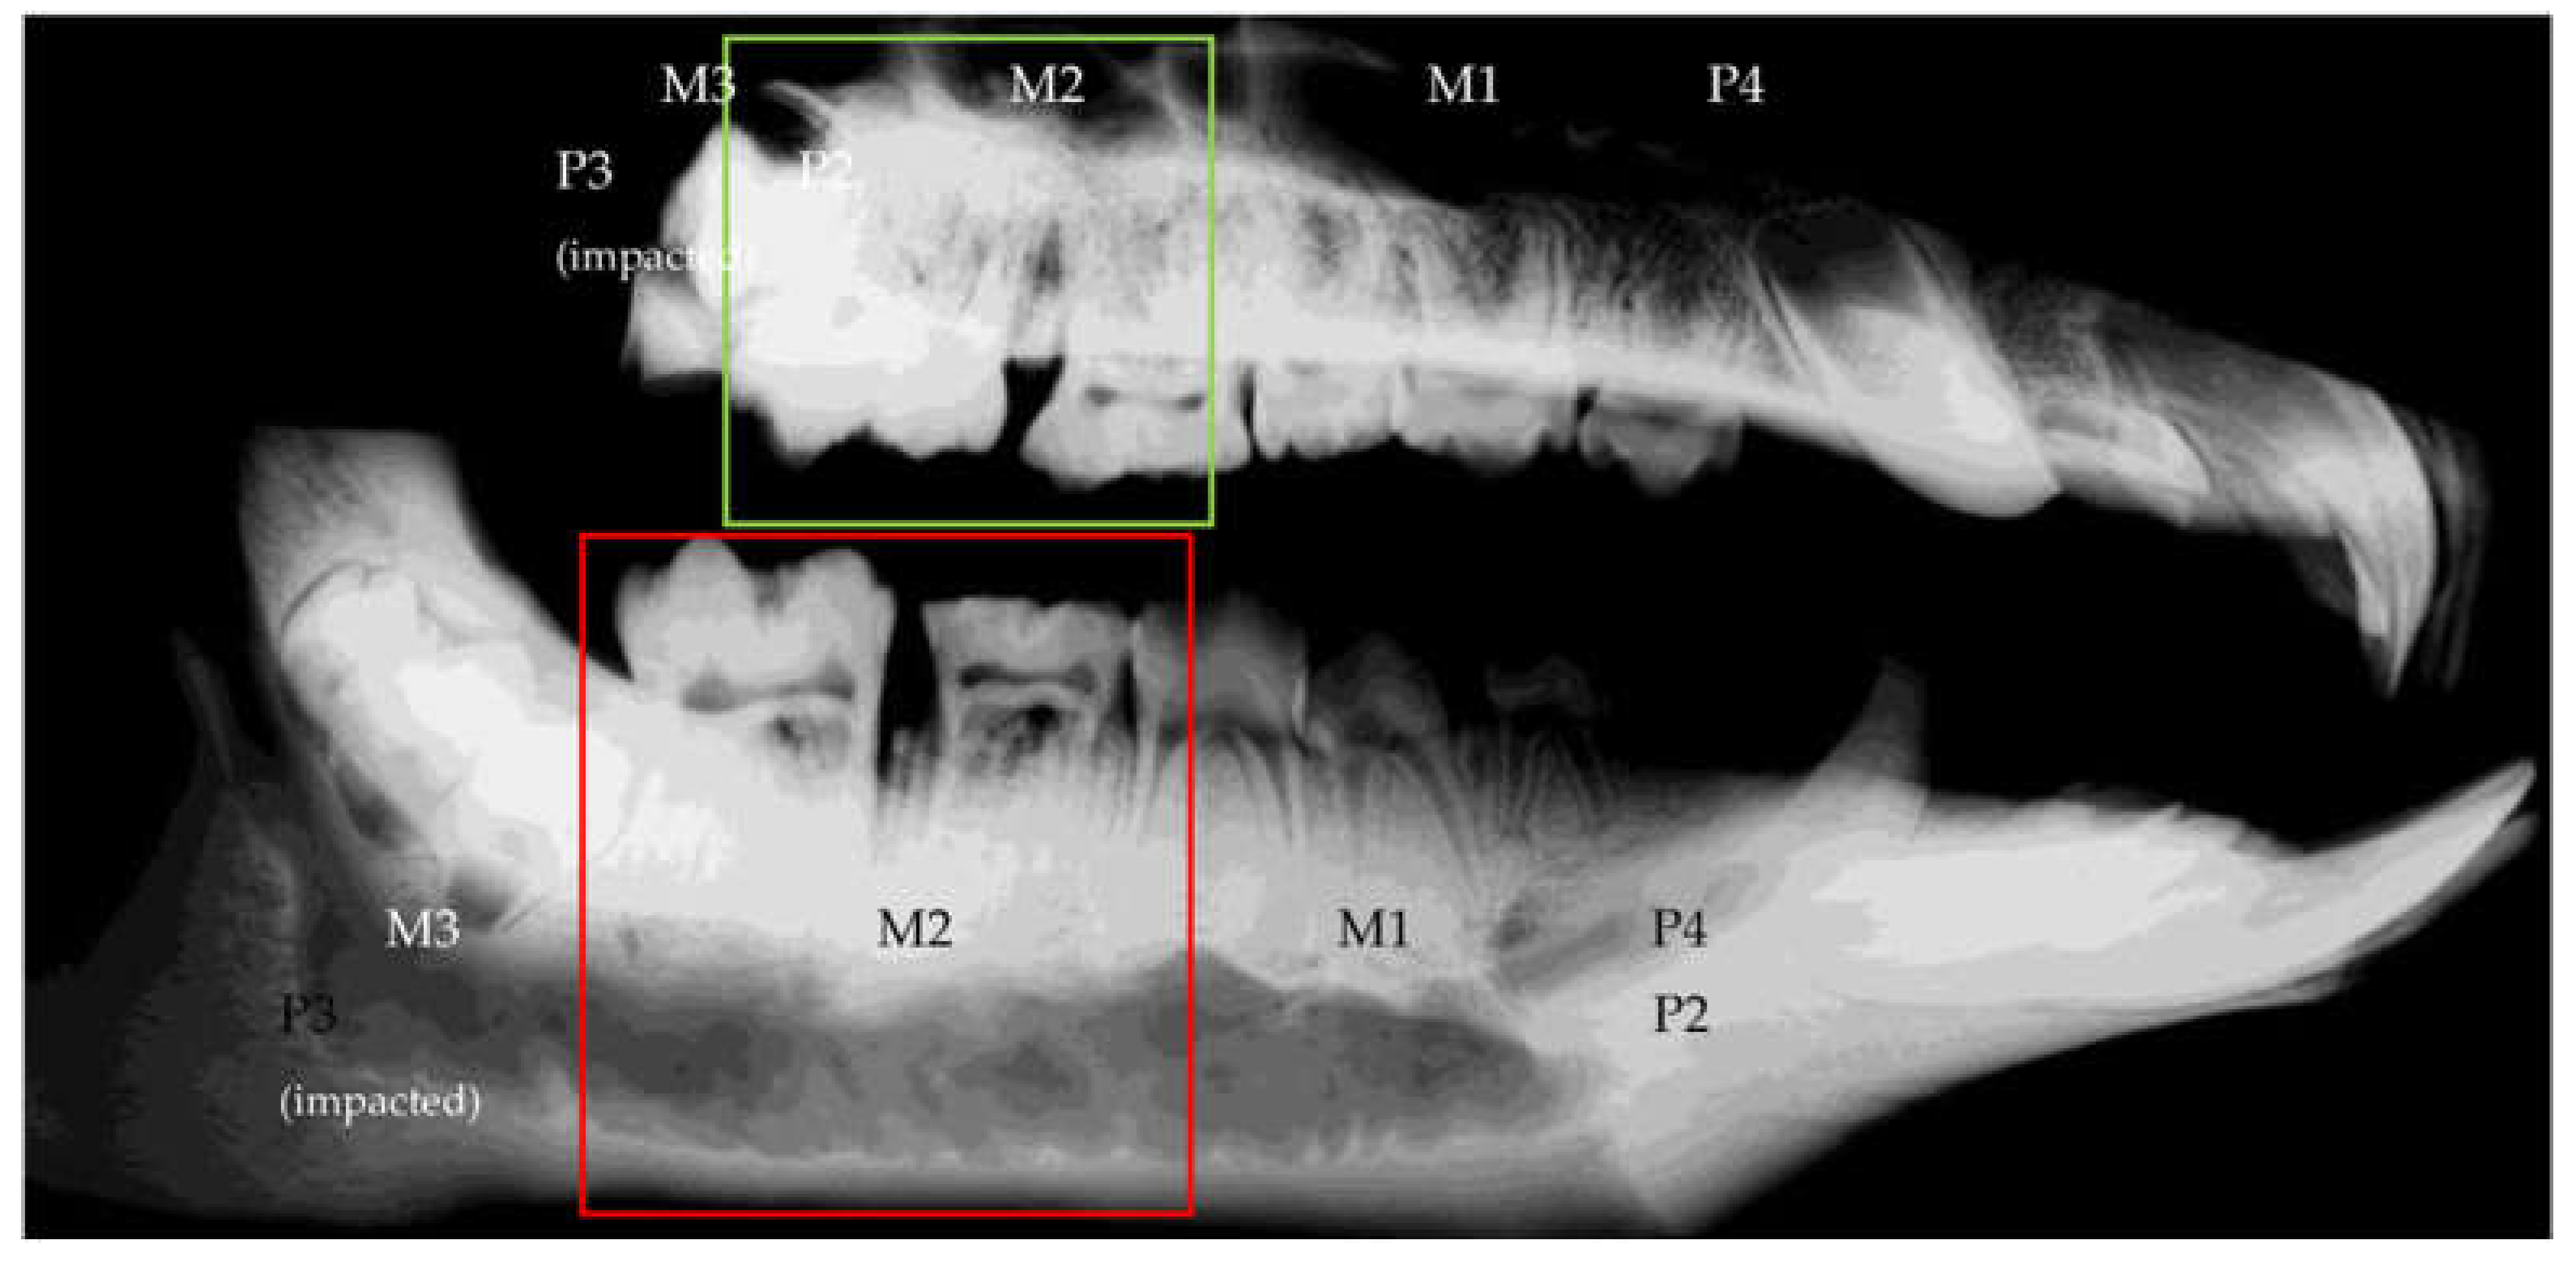

3.2.3. Radiological Evaluation